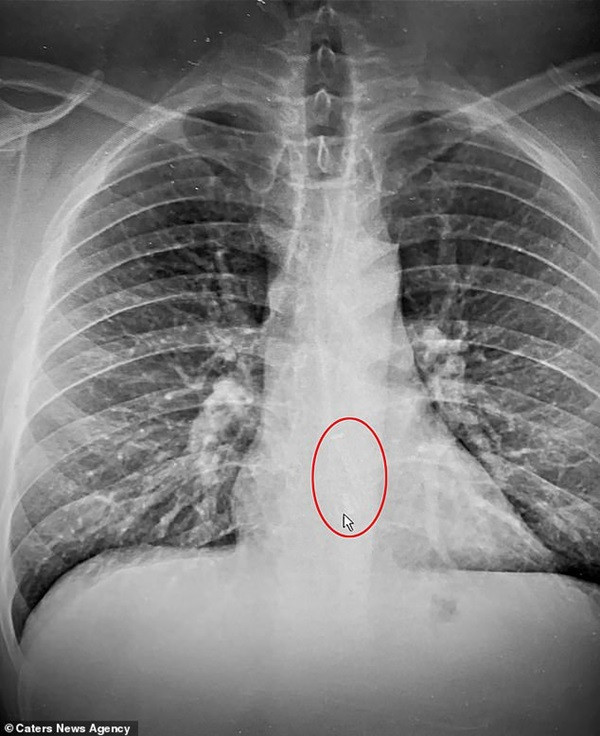

Ban đầu, các bác sĩ cho rằng anh Brad có thể khó chịu như vậy do tối hôm trước anh ăn nhiều món ở một bữa tiệc sinh nhật. Thế nhưng, phim chụp X-quang đã sớm cho thấy rằng bác sĩ nhận định sai và cảm giác của Brad mới đúng: Một chiếc AirPod đang mắc kẹt ở thực quản của anh.

Vị trí chiếc AirPod mắc kẹt trong thực quản. Ảnh: Caters News Agency. Brad vẫn còn rất may mắn vì vị trí mà chiếc AirPod bị mắc đã khiến nó không gây thêm “thiệt hại” gì. Chứ nếu nó mắc vào đường thở thì vấn đề sẽ nghiêm trọng hơn nhiều.